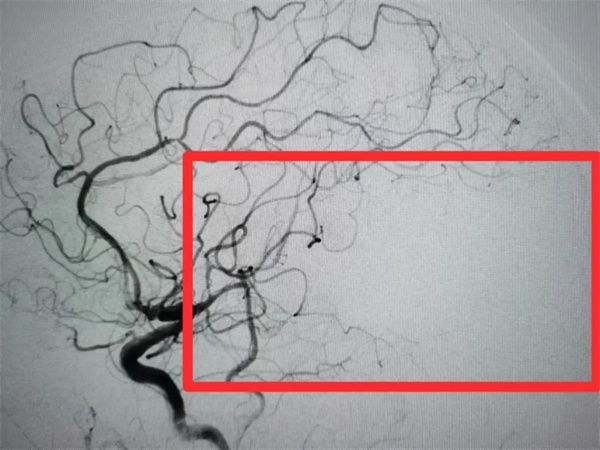

张大爷今年82岁2023年10月13日上午10时30分在劳动中突然出现失语伴右侧上下肢无力,发病2小时即被家人送达我院,医院立即启动“急性脑卒中救治绿色通道”,神经内科方茹主治医师指挥迅速完成头颅MRI、头颈CTA等相关检查诊断为“大面积脑梗死、心房颤动、高血压病、左侧大脑中动脉M1段下干闭塞(图一)”,NIHSS评分10分,因张大爷既往出现过脑出血,有静脉溶栓禁忌,而有机械取栓介入手术指征,方茹主治医师迅速将张大爷病情汇报给动脉盛守权主任医师取栓团队,经评估并与患者家属沟通,同时积极完善术前准备。15:50,手术在全麻下开始,15:56完成股动脉穿刺,16:50抽吸出血栓一枚,闭塞的血管成功再通(图二)。术后给予密切监护、抗血小板治疗后改抗凝治疗、稳定斑块、脑保护、对症等治疗处理10月24日,张大爷出院时可独立行走,遗留轻度失语。